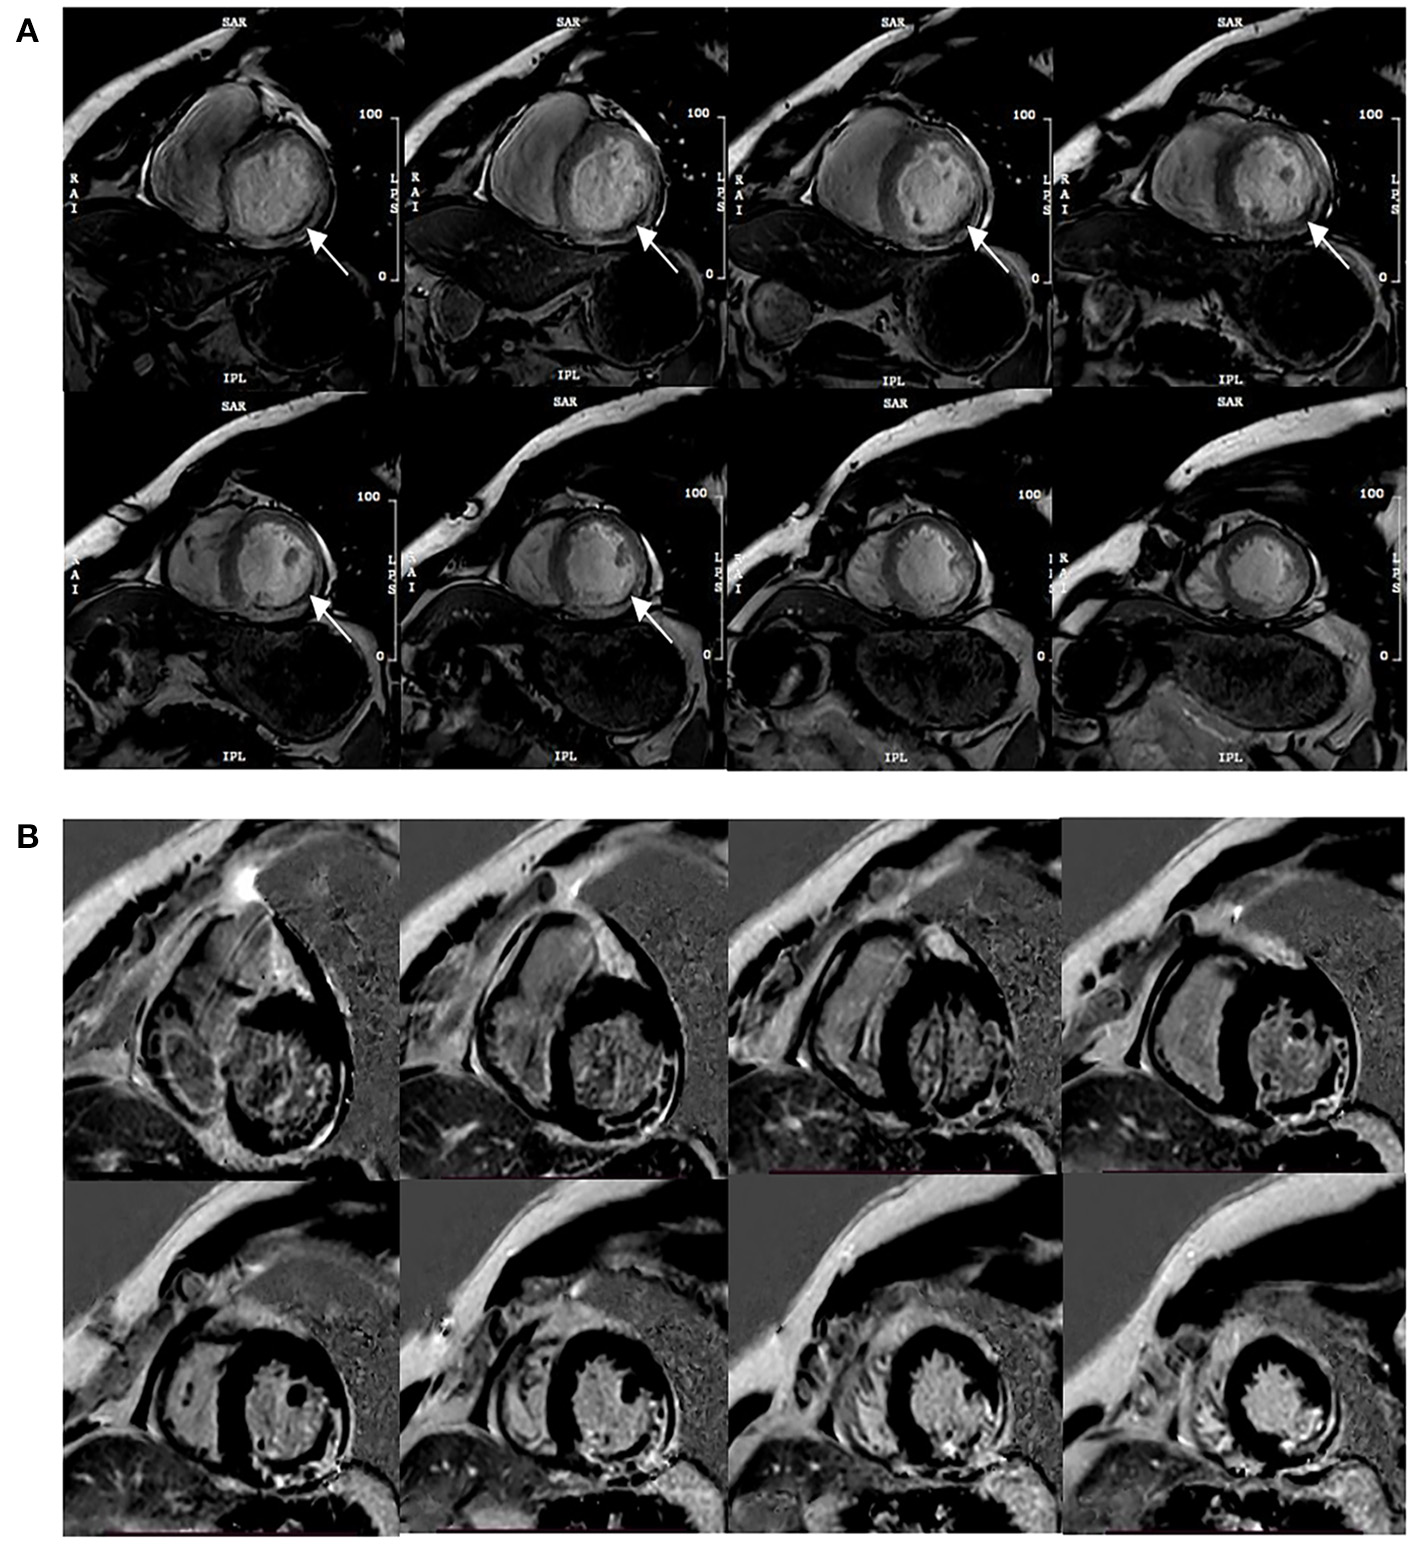

Functional parameters were assessed on short-axis views, and papillary muscles were assigned to the LV volume, such as LVEF, end-diastolic volume (EDV), end-systolic volume (ESV), and stroke volume (SV). MVO recognition could be achieved during the visually corrected tracking performance without an additional MRI method to make a more reliable assessment. The area at risk (AAR) in CE-cine SSFP images was a visual hyperintensity area compared with the remote myocardium (10). MVO was defined as middle or subendocardial dark areas within AAR. To eliminate low signal artifacts similar to MVO areas, a “true MVO” was defined as a dark area surrounded by the constantly visible hyperintensity zone and located at the same position within the cardiac wall on each SSFP image during the complete cardiac cycle (11) (Figure 1). IS was expressed as a percentage of LV myocardial mass (LVMM), measured from short-axis LGE images (signal intensity > 5 SD of unenhanced remote myocardium) (12), and included MVO. Myocardial strain parameters were obtained from the long-axis cine and short-axis cine to calculate the peak strain parameters in diastole, such as the global peak longitudinal strain (GLS), global peak circumferential strain (GCS), and global peak radial strain (GRS).

Figure 1

Typical MVO appearance on contrast-enhanced cine (CE-SSFP) imaging at the same slice position during the cardiac cycle (A), and the corresponding LGE images (B). Arrows point to the dark area surrounded by the hyperintensity infarction zone constantly visible and located at the same position within the cardiac wall on each SSFP image during the cardiac cycle.